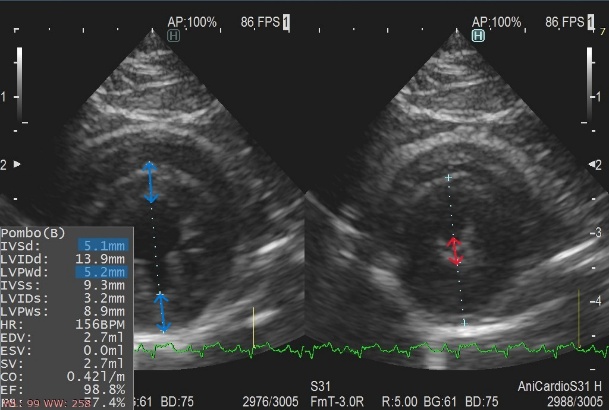

肥大型心筋症は、左心室の筋肉が過剰に分厚くなってしまい、心臓がうまく動けなくなってしまう病気です。原因のほとんどは遺伝であり、アメリカン・ショートヘアやメイン・クーンで多いといわれていますが、すべての猫で発症する可能性があります。発症の年齢も若齢から高齢まで様々です。

心筋が肥大して左心室の内径が極端に狭くなることで、左心房に血液が渋滞し、血栓を形成することがあります。この血栓が、後ろ足の付け根の動脈に詰まることがありますが、多くは何の前触れもなく発症します(動脈血栓塞栓症)。突然、後ろ足に麻痺を伴う激痛が走り、そのまま突然死となってしまうこともあります。